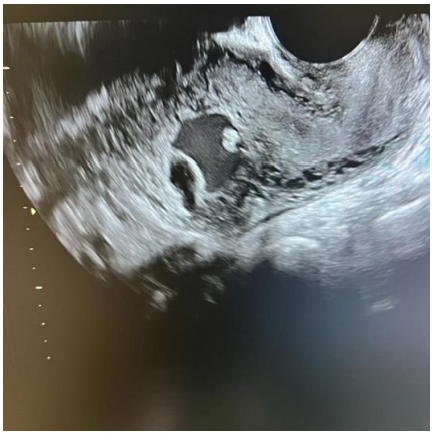

A 16-year-old lady, para 0+2 presented to the emergency department complaining of active vaginal bleeding after medical treatment of missed miscarriage. She had history of two recurrent miscarriages treated by surgical evacuation. Her pregnancy was spontaneous. Her medical history was unremarkable. Clinically she was vitally stable, soft abdomen, no tenderness no palpable masses. Speculum examination was suggestive of normal-looking cervix with bleeding from the os, uniformly enlarged 8 weeks size uterus freely mobile, no cervical movement tenderness, and no adnexal masses. An ultrasound demonstrated a gestational sac about 2.2 cm in diameter. It showed also a yolk sac and a fetal pole of 8 mm without cardiac cavity. Surgical suction and evacuation was performed under ultrasound guidance.  During the evacuation, the gestational sac was noted to be below the suction tube, the procedure was aborted. The intrauterine products were sent for histology which showed fragments of endometrium, blood clots and fibrosed chorionic villi, no evidence of malignancy. Upon reassessment, she was still complaining of the vaginal bleeding. Beta human chorionic gonadotropin was 1450. A Trans abdominal & trans vaginal ultrasound scan showed empty cavity with thick endometrium, a gestational sac below the line of endometrium with a yolk sac and fetal pole without cardiac activity, embedded in the myometrium (Fig.1&2&3&4) .The use of 3-D ultrasound helped in confirming the diagnosis of intramyometrial pregnancy, providing highly informative and detailed imaging to support accurate clinical assessment (Fig.5&6). In view of her parity and future fertility medical treatment was discussed with and accepted by the patient. Methotrexate was administered with a single dose of 50mg given intramuscularly on day 7, the drop was less than 15%. The patient received a second dose of methotrexate .The patient was displaced due to war circumstances. She then continued to have serial pregnancy tests, not able to have quantitative B-HCG test. Her pregnancy test became negative eventually then her menstrual cycle resumed back with regular intervals.

FIG.1

FIG.2

Figure 1

Figure 2